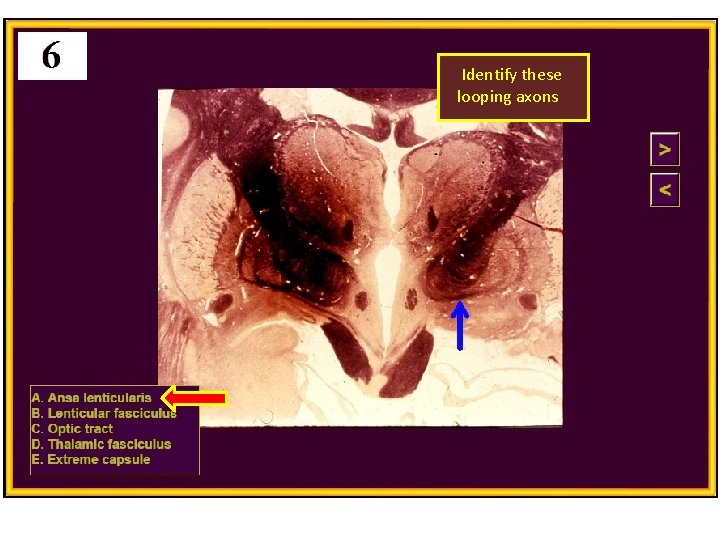

Identify these looping axons

(Transmits vsct)